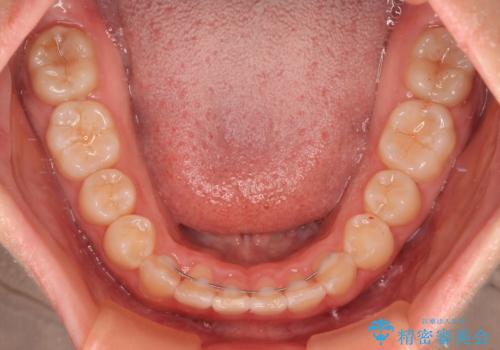

- 上下前歯のデコボコを気にして来院された患者様です。

叢生は軽度であり、ワイヤー矯正でもマウスピース矯正でも対応可能であったので、好きな装置を選んでもらいました。

相談の結果、インビザラインによる矯正治療を行うこととしました。

毎日の装着時間をしっかりと守っていただいたことで、1年程度で無事に治療を終えることができました。